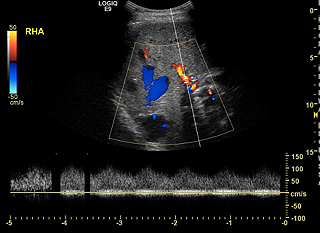

Ultrasound depicting a

Liver Arteriovenous Malformation (AVM).

A liver ultrasound uses reflected sound waves to produce a picture of the organs in the abdomen. No radiation is used during this study, and it is therefore the preferred method for screening liver AVMs.